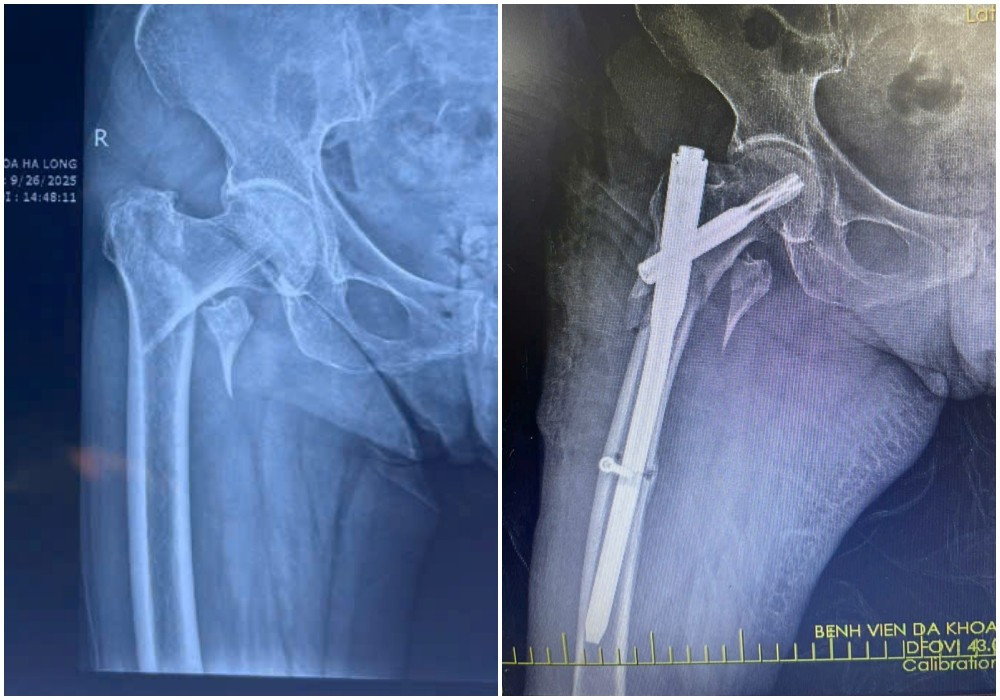

Hình ảnh X-quang gãy liên mấu chuyển xương đùi phải của bệnh nhân N (87 tuổi) được kíp mổ phẫu thuật kết hợp xương ít xâm lấn - Ảnh BVCC

Kết quả chụp X-quang xác định bệnh nhân bị gãy liên mấu chuyển xương đùi. Với tình trạng tuổi cao, sức yếu, việc vận chuyển bệnh nhân hạn chế, tiềm ẩn nguy cơ làm vị trí gãy thêm trầm trọng.

Qua đường rạch da nhỏ khoảng 3-5cm, phẫu thuật viên nắn chỉnh xương gãy về vị trí giải phẫu, sau đó cố định bằng đinh nội tủy PFNA dưới màn hình tăng sáng (C-arm).